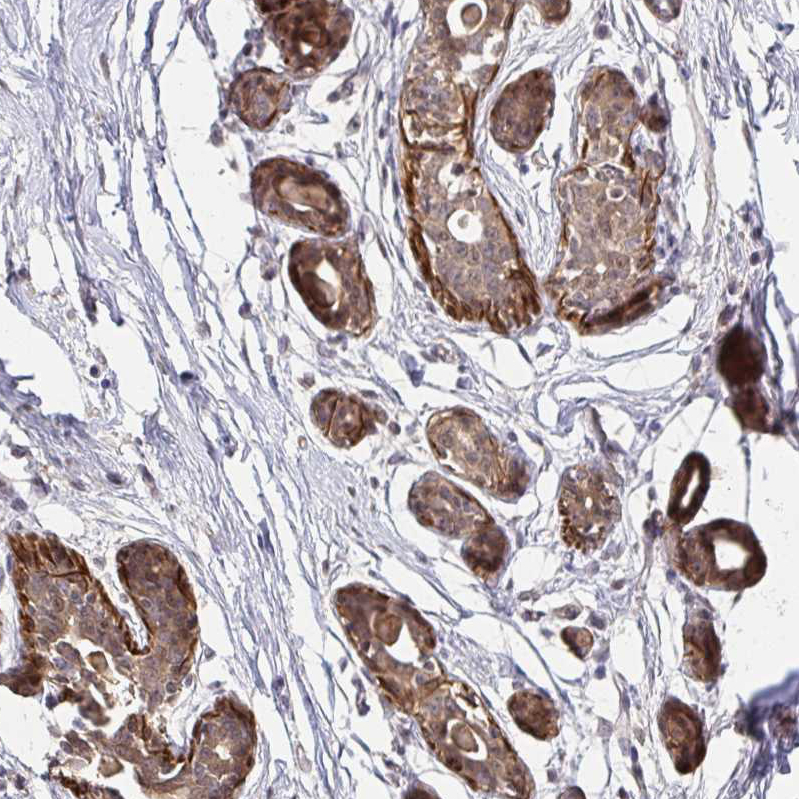

Immunohistochemical staining of human breast shows strong cytoplasmic positivity in glandular cells.